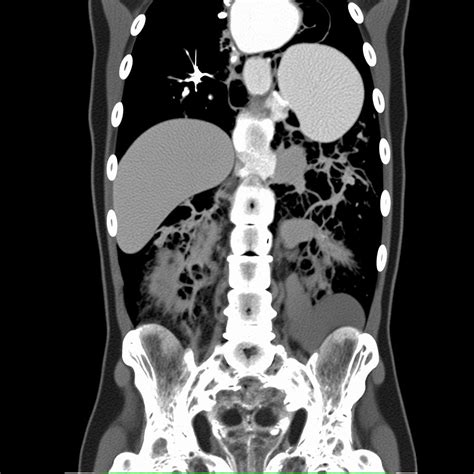

Understanding the pancreas on CT scans is crucial for diagnosing and managing various pancreatic conditions. Computed Tomography (CT) scans provide detailed images of the pancreas, aiding in the detection of diseases such as pancreatitis, pancreatic cancer, and cysts. This blog post will delve into the importance of CT scans in pancreatic imaging, the preparation required for the procedure, and the interpretation of results.

CT scans are a cornerstone in the diagnostic process for pancreatic diseases. They offer high-resolution images that can reveal abnormalities in the pancreas, such as inflammation, tumors, or cysts. The detailed visualization provided by CT scans helps healthcare professionals make accurate diagnoses and develop effective treatment plans.

Radiologists also evaluate the surrounding structures, such as the liver, spleen, and blood vessels, to determine if the disease has spread or affected other organs.